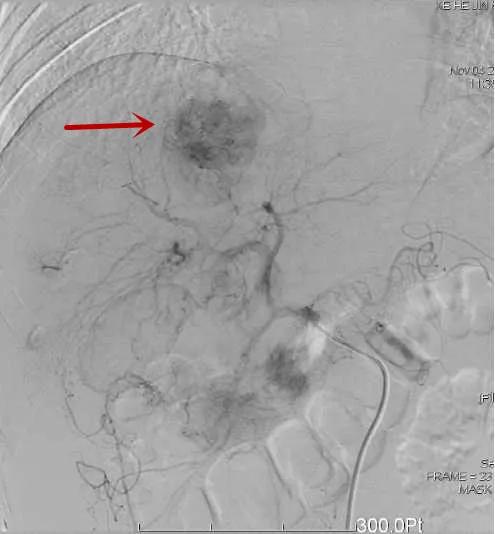

肝癌破裂出血介入止血

△肝内肿瘤破裂出血/栓塞后造影示肿瘤出血已止住